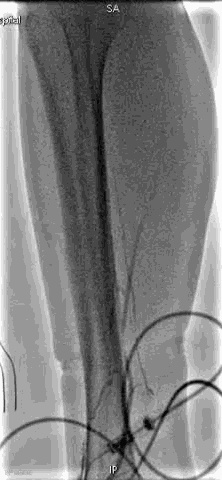

手术过程

抽吸结果